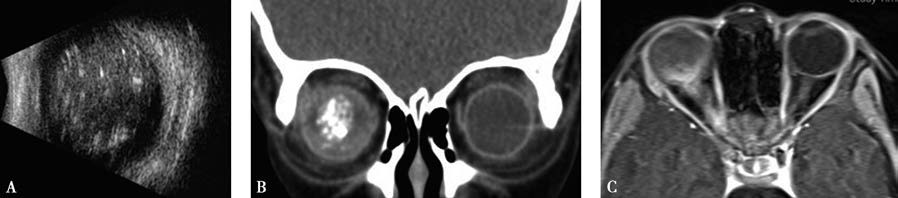

Figure 2 Imaging findings in a child with RB

A. Ocular ultrasound shows an echogenic mass with variable intensity in the right vitreous cavity, accompanied by calcifications.

B. CT reveals calcified foci within the right intraocular tumor.

C. MRI shows thickening and enhancement of the right optic nerve.

MRI offers higher resolution for soft tissue contrast and is currently the most sensitive imaging technique for evaluating orbital or extraocular extension of RB.